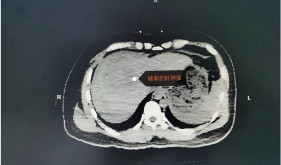

开平这场高龄+驼背+肠癌手术!吸引全国5000余名同行在线观摩…